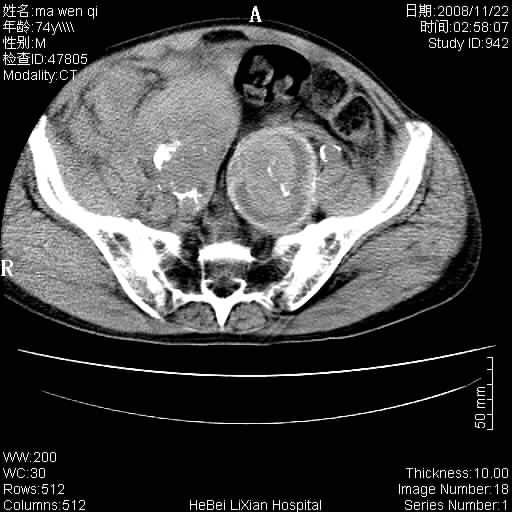

患者男 74岁.突然昏迷,休克6小时.血压70/30,头颅ct未见异常,既往体健.

补充病史,保留导尿10小时,尿袋内只有少许尿液,患者于住院后15小时后去世.

腹主动脉、双侧髂动脉夹层动脉瘤破裂出血进入腹腔。

1)考虑双侧髂动脉瘤并右侧动脉瘤破裂出血,右侧腹膜后及腹腔积血。2)双侧腹股沟疝。

1)考虑,腹主动脉、双侧髂动脉夹层动脉瘤破裂伴右侧腹膜后及腹腔积血。2)双侧腹股沟疝。

1)考虑胸、腹主动脉、双侧髂动脉瘤并右侧动脉瘤破裂出血,右侧腹膜后及腹腔积血。2)双侧腹股沟疝。

考虑双侧髂动脉瘤并右侧动脉瘤破裂出血,右侧腹膜后及腹腔积血;难见病例。谢谢